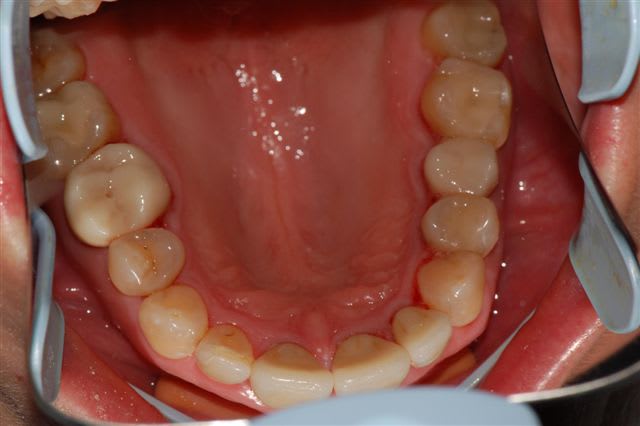

voici un cas traité en dentisterie globale à l'aide du laser en paro et du cerec en occluso, le cas à été terminé en 2010, cette semaine examen microbiologique de routine avec maintenance paro, il n'y a plus de flore pathologique dans la bouche de cette patiente

Emma

Reste plus qu'à faire des greffes de gencives secteur 4.

Tu as une radio zone 11-21, perte de papille importante.

salut ceramik, toujours aussi contente de te lire, tes désirs sont des ordres, radios faites en 2010, les photos dates de juin 2010, les papilles entre 11 et 21 sont entrain de se reconstruire petit à petit, au prochain contrôle de maintenance, je ferai des radios et des photos pour montrer l'évolution engendrée par la biostimulation laser diode.

Joli cas Emma, juste une remarque, le travail de l'espace inter incisif en jouant sur la convexité des profils d'émergence masquerait le manque immédiat de papille et à terme la papille se reconstruirait plus rapidement.